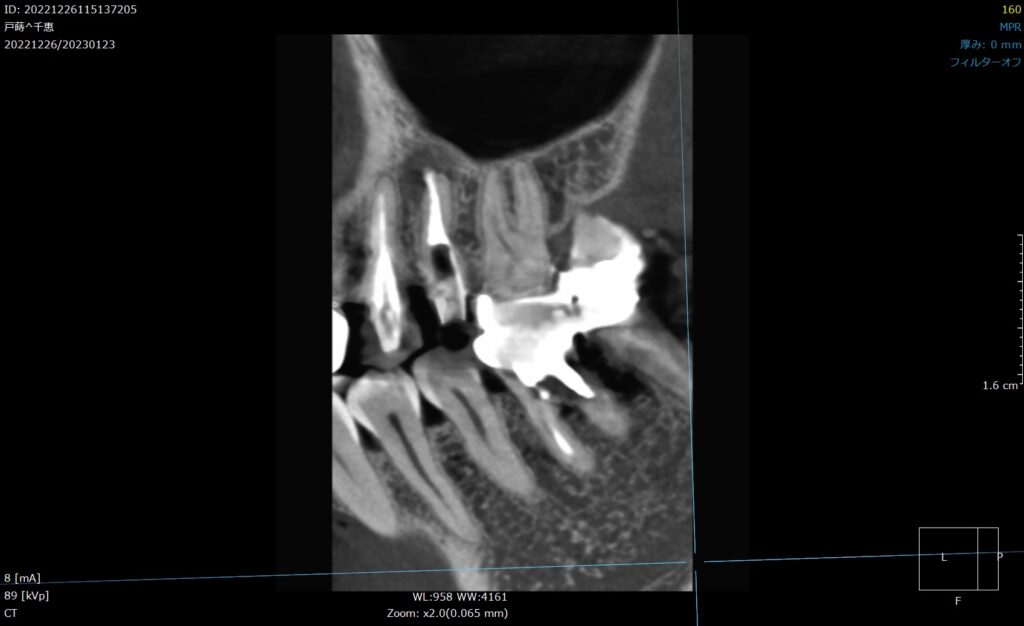

メタルコアCT画像

CT撮影で見るとこのような状態です。

メタルコアの輪郭

赤は歯の輪郭で、青がメタルコアの輪郭です。

歯の幅の7割くらいのメタルコアが入り込んでいます。

メタルコア先の膿

そして根の先には膿が溜まっている像が認められます。(赤枠)